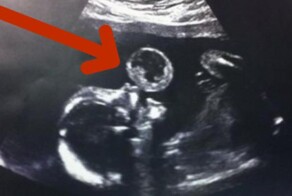

- На УЗИ видно, как малыш надувает пузырь. То, что врачи сказали матери, бросает в холодный пот